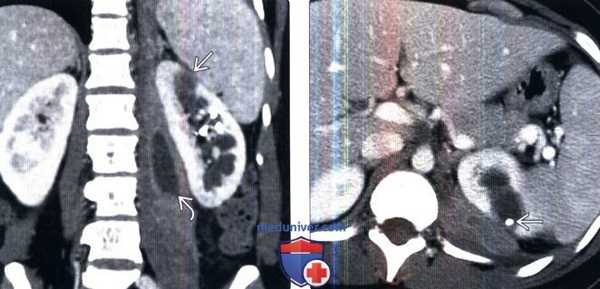

(Слева) КТ с контрастированием, коронарная проекция: у женщины 32 лет, поступившей с болью в боку, лихорадкой и позитивным бактериальным посевом крови на Е. coli, выявлены гематогенные стафилококковые абсцессы левой почки и левой поясничной мышцы.

(Справа) КТ с контрастированием, аксиальная проекция: у этой же пациентки визуализирован чрескожный дренажный катетер внутри абсцесса почки. После дренирования отмечено полное восстановление.